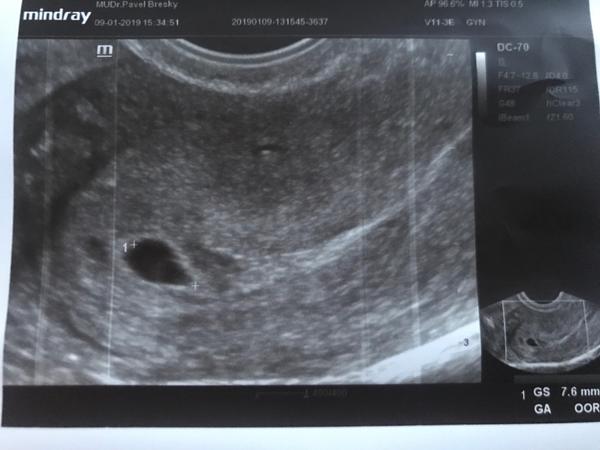

Ja mela 4+5 jen gestacni vacek a pak sem byla az 6+0 a to uz bilo srdicko🙂

Srdicko bilo v 5+6 a vim stari tehotenstvi presne, bylo po ivf.

Fyzicky srdecni akce u ditete uz je, ale utz to nedokaze zachytit = zalezi na pristroji, kazdopadne je tohle brzo. S jistotou 7+ je krasne videt vzdy.

Srdecni akce nejdriv cca 6+1, s jistotou cca 6+3, ale musi to byt podle ovulace, ne podle menstruace. Udaj podle menstruace je naprosto nepresny.

Srdeční akce v 5.tt. je, ale druhá věc je ta, odkdy ji zachytí UZ. A to záleží na typu přístroje a taky na zkušenostech doktora. Spíš bych ji ale ještě nečekala.

Já byla na utz včera a byla jsem 4+6tt a vidět nebylo absolutně nic jen místo kde je miminko...